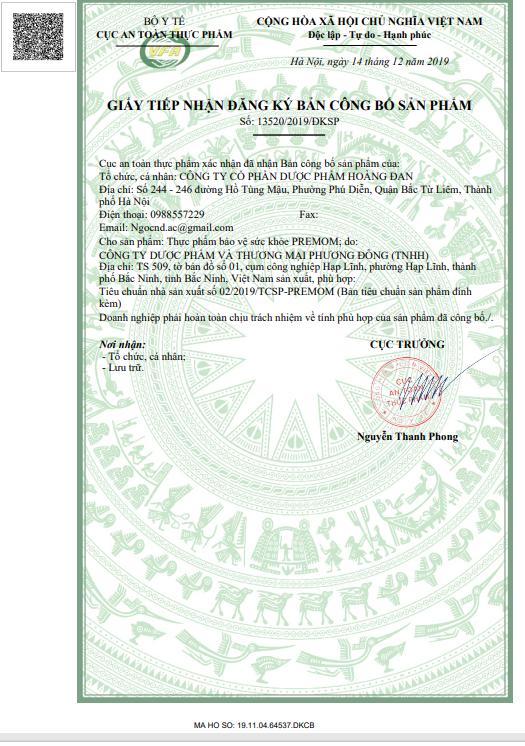

Công ty Cổ phần Dược phẩm Hoàng Đan

Địa chỉ: 244 - 246 Hồ Tùng Mậu, Quận Bắc Từ Liêm, Hà Nội